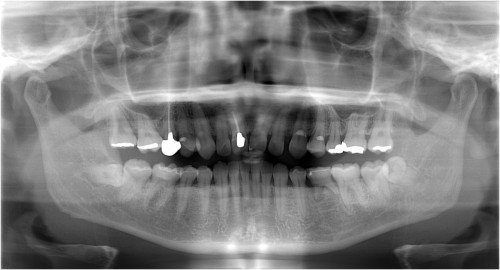

術前

左下5部 乳歯晩期残存

抜歯後

インプラント埋入直前

インプラント埋入直後

埋入後約3ヶ月

オペ時のISQ値

土台装着

被せ物装着

被せ物装着後